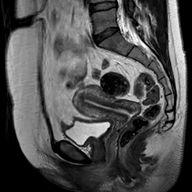

当院のMRIで次のような画像を撮影することができます。